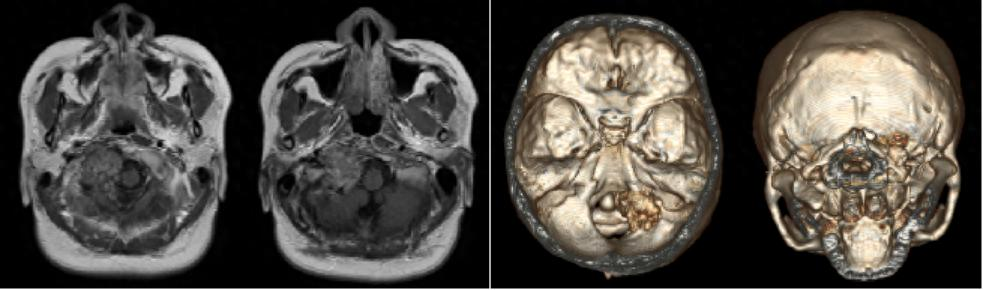

术后第二天,小兰已经可以下地活动和正常进食了,咳嗽反射也表现良好术后复查头CT、MRI及颈部平片示术区无出血、肿瘤完整切除;枕颈固定装置位置及颈椎曲度均良好此次手术的实施,是医院神经外科综合实力的集中展现。